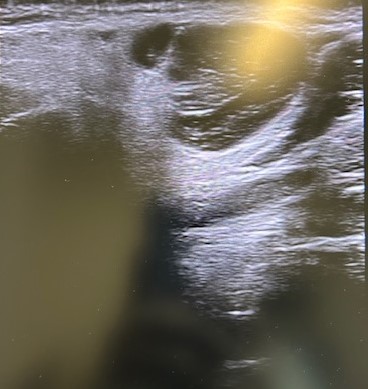

Ecografía POCUS: imagen heterogénea 1,9 x 1,7 asimétrica, con tabique en su interior, y captación de color (en modo C o con Doppler). Ante datos de mal de pronóstico solicitamos PAAF, analítica y ecografía reglada preferente.